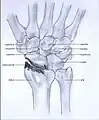

Stages

Post-traumatic osteoarthritis can be classified into four stages.[1][6] These stages are similar between SLAC and SNAC wrists. Each stage has a different treatment.

- Stage I: the osteoarthritis is only localized in the distal scaphoid and radial styloid.

- Stage II: the osteoarthritis is localized in the entire radioscaphoid joint.

- Stage III: the osteoarthritis is localized in the entire radioscaphoid joint with involvement of the capitolunate joint.

- Stage IV: the osteoarthritis is located in the entire radiocarpal joint and in the intercarpal joints. It also may involve the distal radio-ulnar joint (DRUJ).

Stage I

Stage II